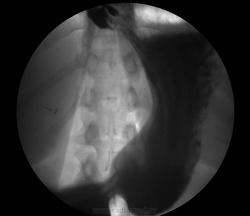

Молодая женщина, беспокоит чувство тяжести, распирания в эпигастрии после приема пищи, которые появились не так давно. Пришла на скопию желудка. Прошу прощения за качество фото. Грыжа ведь?

Судя по кадрам на ЭЛЕКТРОНе работаете. Не утверждал бы с уверенностью, что грыжа. По первым кадрам подумал бы о грудном желудке. Грыжу ищем лёжа на животе, пациент пьёт барий и при прохождении через кардию просим натужиться.

А третий кадр уверенность в грыже разве не добавляет?) Желудок почти весь на месте, в брюшной - совсем не похож на грудной?